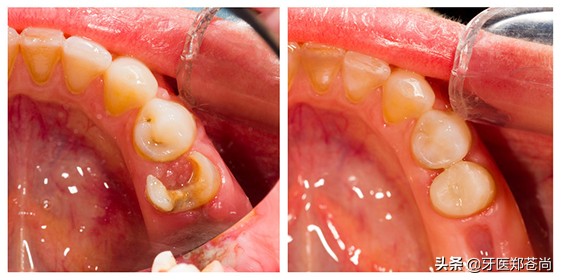

慢慢的,蛀牙发黑的程度加重,开始有个小牙洞;

深入发展后,蛀牙经常疼痛,牙洞又大又深;